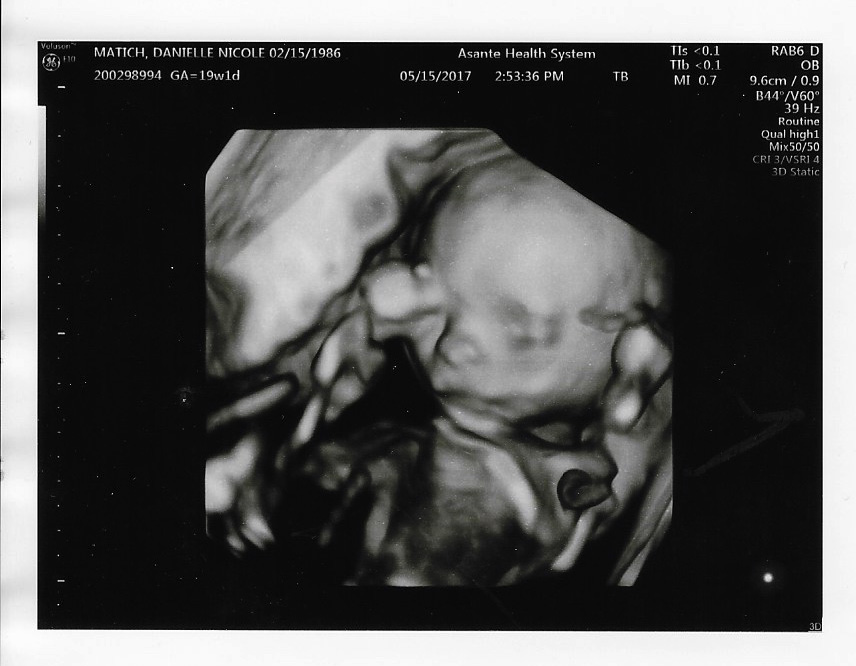

Lil 19 weeks 02 Published September 5, 2017 at 856 × 666 in The Baby! ← Previous Next → Like Loading...